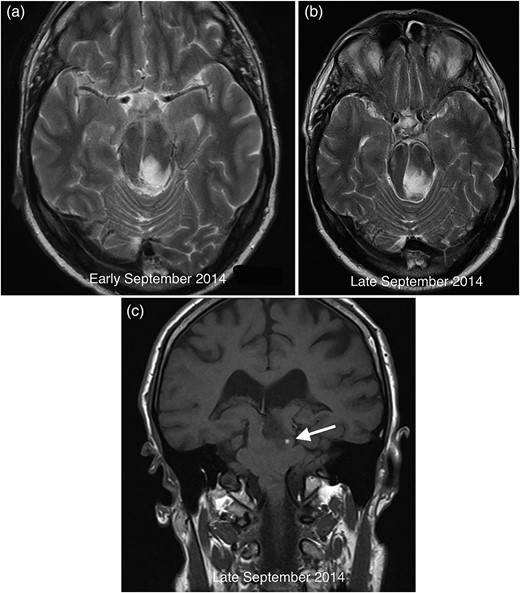

After biopsy, the specimen showed profuse haemorrhage, thought to be secondary to the procedure itself. The specimen showed no evidence of malignancy, but reactive features with a small volume of fresh haemorrhage and engorged vessels. A GFAP stain revealed severe gliosis, with spider-shaped reactive glia (Fig. 3).

Grey matter parenchyma sample (a) consistent with brainstem biopsy showing prominent vessels and a small volume of haemorrhage. The GFAP stain (b) within the same sample confirms severe gliosis featuring spider-shaped reactive glia.